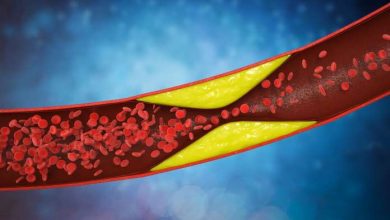

5 segnali che ti dicono che hai il colesterolo alto

I sintomi di colesterolo alto sono diversi e possono rivelarci di avere qualche problema anche senza gli esami del sangue,…